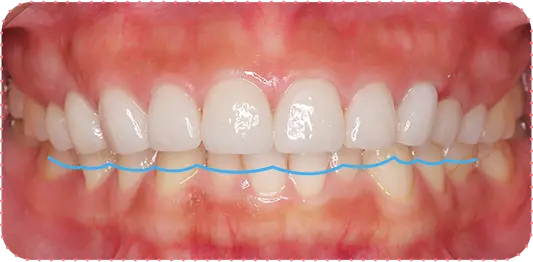

Before

After

主訴

前歯をインプラントにしてほしい

治療期間

8か月

治療費

約150万円

治療内容

右上1番と左上1番をインプラント、右上2番をラミネートべニア、左上2番をセラミッククラウンにて修復

治療のリスク

治療後に口腔内管理が不適切な場合、埋入したインプラントが感染・炎症を起こす可能性があります。

しみたり、違和感が生じることがあります。咬み合わせによっては、セラミックが欠ける可能性があります。